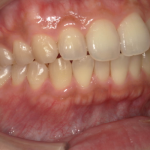

虫歯治療の前にセルフケアの指導とクリーニング・SRPを行い歯周病を改善した症例

治療前 治療後 相談内容 「左上グラグラして昨晩から ...